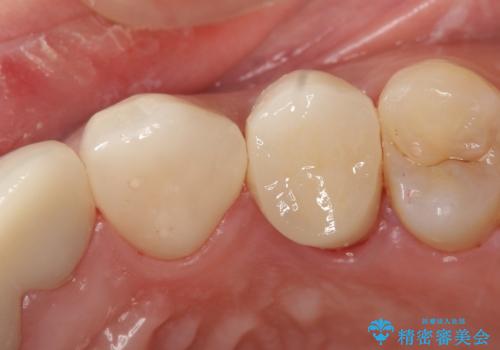

歯ぐきの深い位置まで虫歯が 歯周外科→被せもの による奥歯の治療

多発した縁下カリエス 歯周外科を併用する虫歯治療